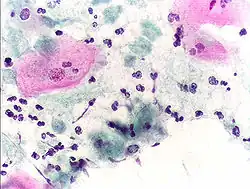

Micrograph of a Pap test showing trichomoniasis. Trichomonas organism seen in the upper right. Pap stain. -

Infestation by Trichomonas vaginalis